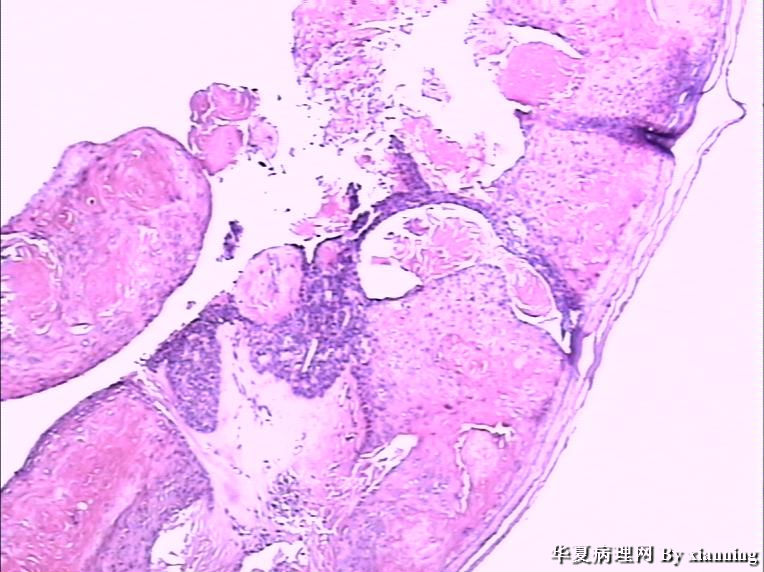

女 50岁 头皮下肿块

巨检:灰白色不规则结节0.9*0.7*0.4cm3,切面灰白色实性质地中等

名称:图1

描述:36580003